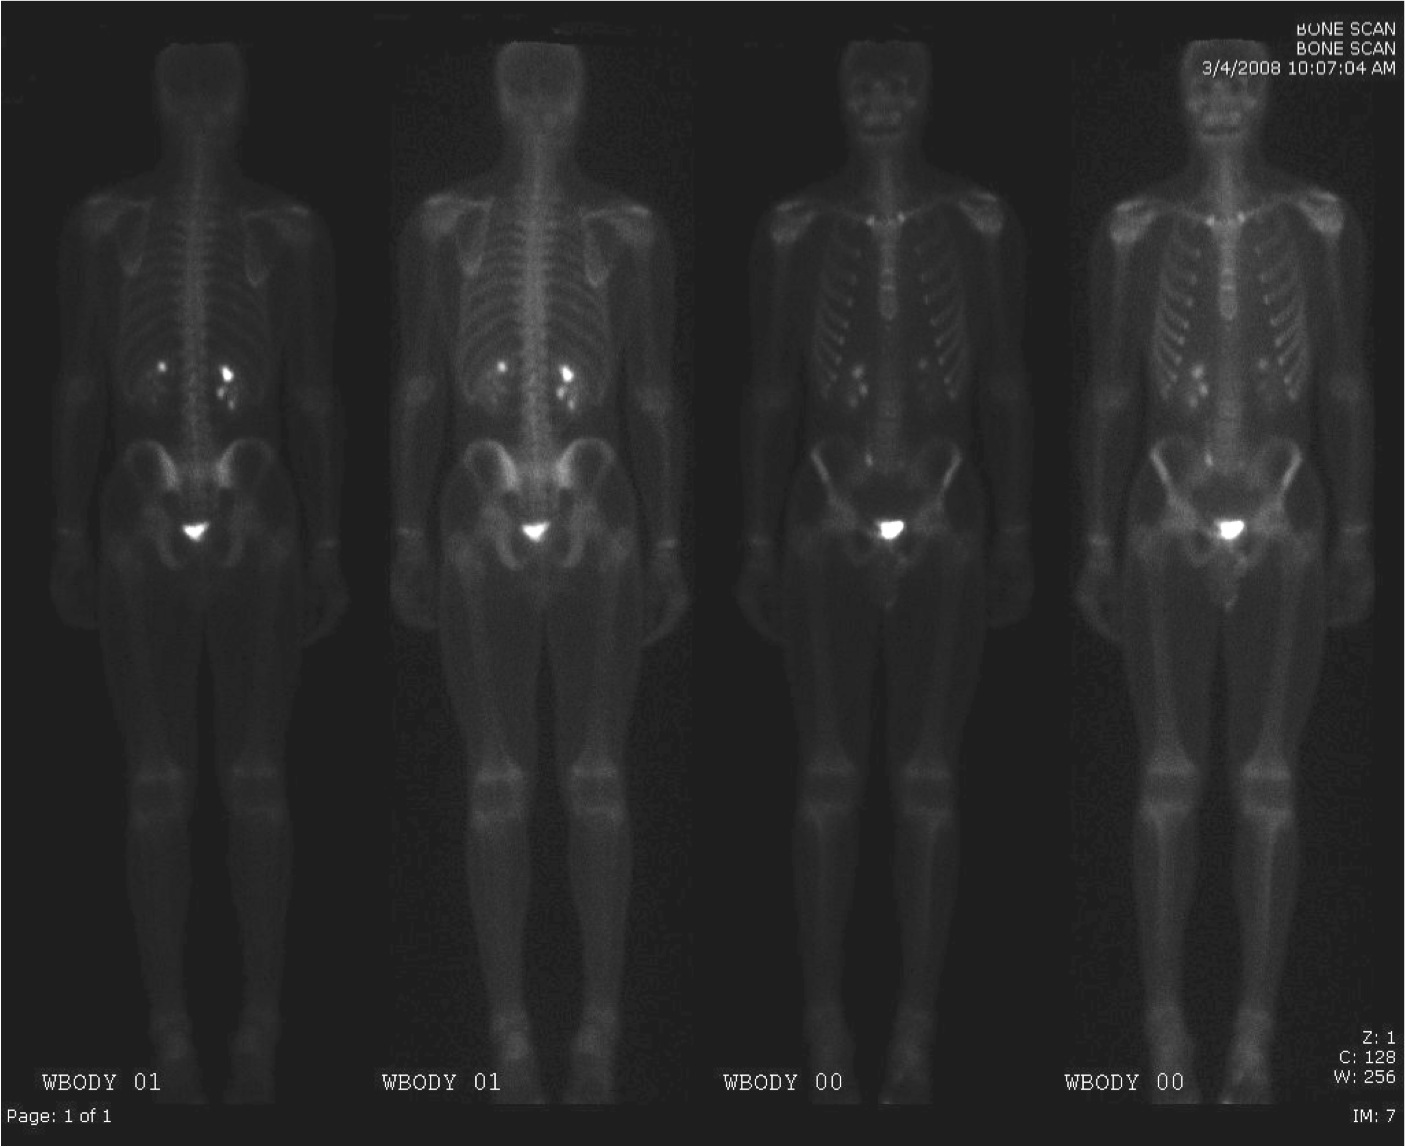

Secondary Bone Cancer Pet Scan Stock Image C034 6925 Science Photo Library

Secondary Spinal Cancer Ct And Pet Scan Stock Image C039 0162 Science Photo Library